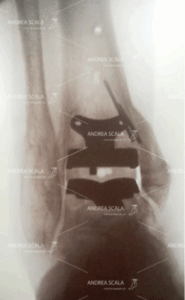

La Figura mostra la visione anteriore delle componenti protesiche “di prova”. L’installazione di queste componenti provvisorie il chirurgo può avere una idea molto precisa del punto in cui si trova l’intervento. Si possono apprezzare:

– la componente tibiale alloggiata nella resezione ossea precedentemente effettuata;

– la componente astragalica alloggiata nella resezione ossea precedentemente effettuata;

– il polietilene di prova.

Questo punto particolare dell’intervento rappresenta la idea più precisa che il chirurgo può avere dell’impianto della protesi di caviglia. La via d’accesso anteriore permette la visione diretta della intera cavità articolare. Il paziente non è di fianco. La gamba e la caviglia del paziente non sono bloccate in un telaio metallico esterno. Gli elementi principali che occorre controllare sono i seguenti:

– controllare visivamente se vi sono ostacoli al corretto movimento articolare a livello del versante tibiale e peroneale;

– controllare che il reciproco movimento delle componenti protesiche sia fluido e proceda senza scatti e senza perdite di contatto reciproche durante il moto;

– controllare l’equilibrio della tensione dei compartimenti legamentosi. I legamenti del compartimento tibiale sono più robusti e solidi, ma non devono fare aderire la caviglia al malleolo tibiale; i legamenti del compartimento laterale (Peroneo Astragalico e Peroneo Calcaneare) non debbono essere troppo lassi e causare instabilità della protesi;

– controllare che la sindesmosi tibio peroneale sia forte e robusta. Quando la sindesmosi è ossificata, non va toccata e va preservata in quanto elemento molto importante di stabilità. La via d’accesso laterale demolisce la sindesmosi.

In questa fase dell’intervento l’operatore ha ancora margini per attuare le modifiche che ritiene opportune.

La figura mostra la visione laterale del “resurfacing” tibiale. Si vede il manico del supporto su cui si appoggia la componente tibiale definitiva, che viene ancorata alla tibia mediante tre ancoraggi appuntiti. Nella figura si vede pure la resezione dell’astragalo preparato per ricevere la componente protesica. Si nota che la resezione dell’osso del paziente è minimale.